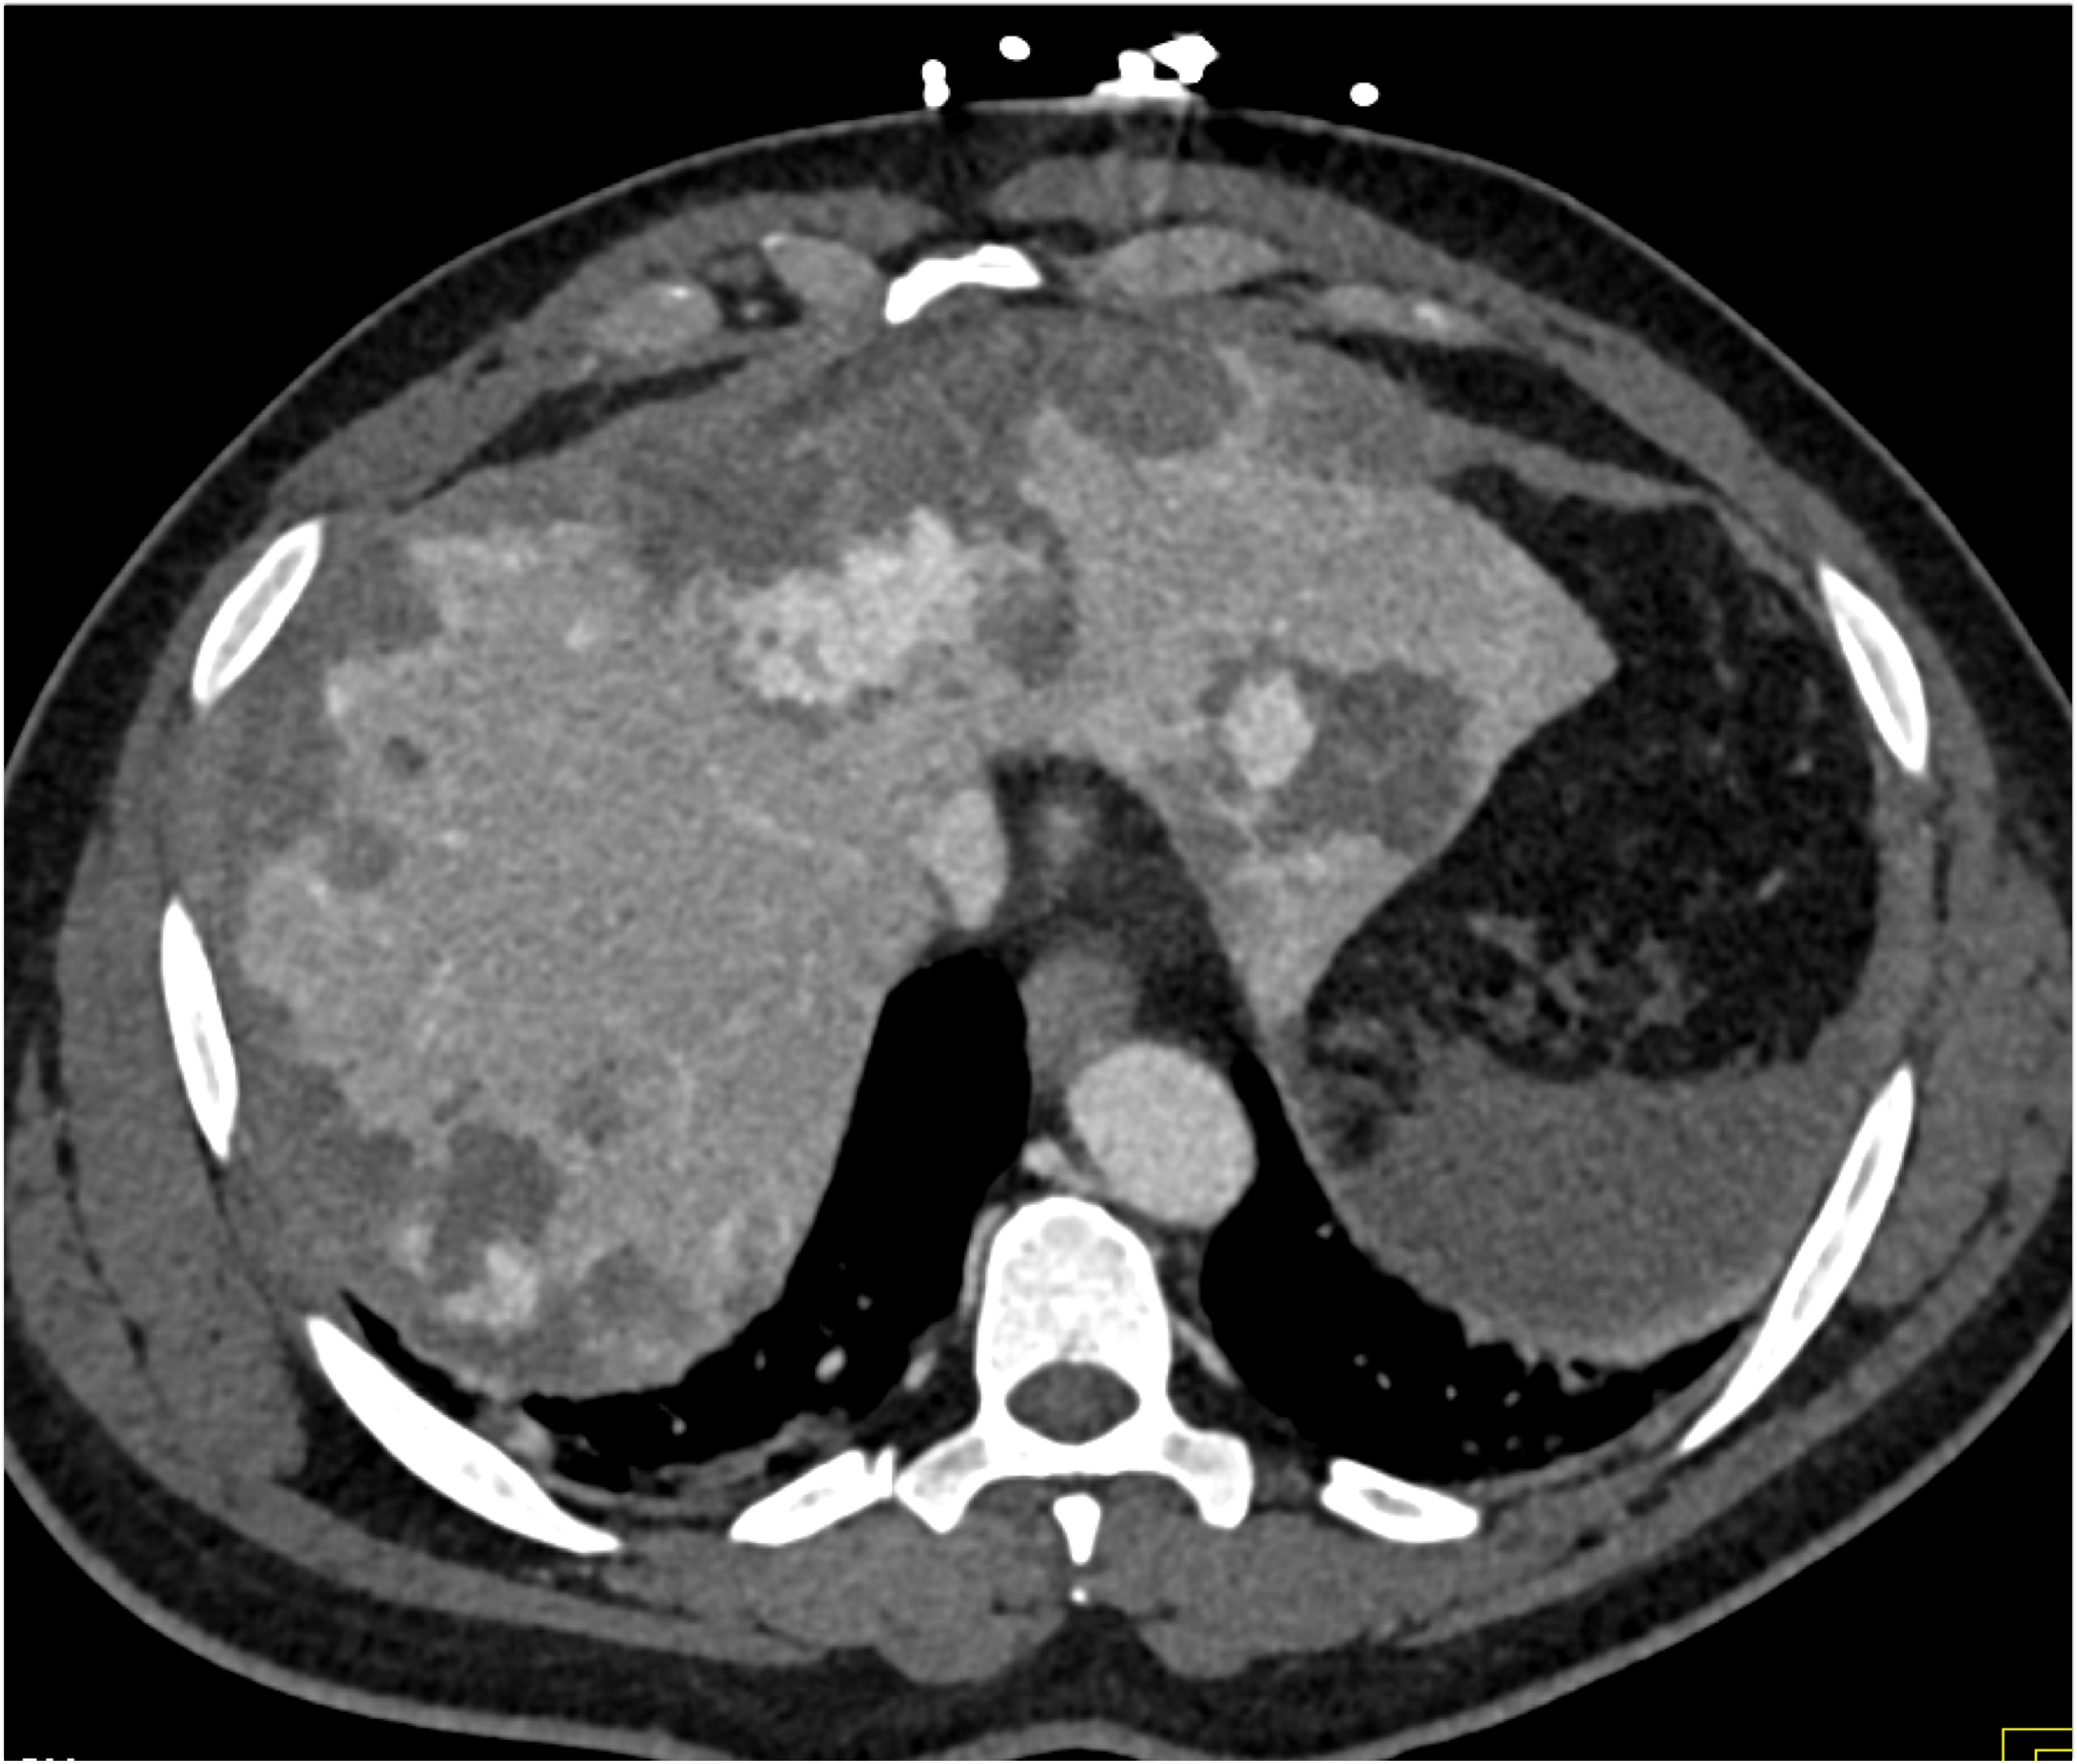

8) In this patient with RUQ pain and no history of trauma the best diagnosis is?

multiple hemangiomas

focal nodular hyperplasia

hepatic adenomas

angiosarcoma of the liver